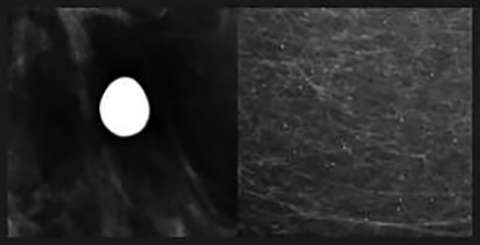

Rim Calcifications

Rim Calcifications: Include the previously described “eggshell” and “radiolucent centered” calcifications. These correspond to calcifications along round lesions such as oil cysts or simple cysts. These are usually associated with history of trauma or surgery.

Round Calcifications

Round Calcifications: Include the previously described “round” and “punctate” calcifications. As the name implies these are round in morphology.